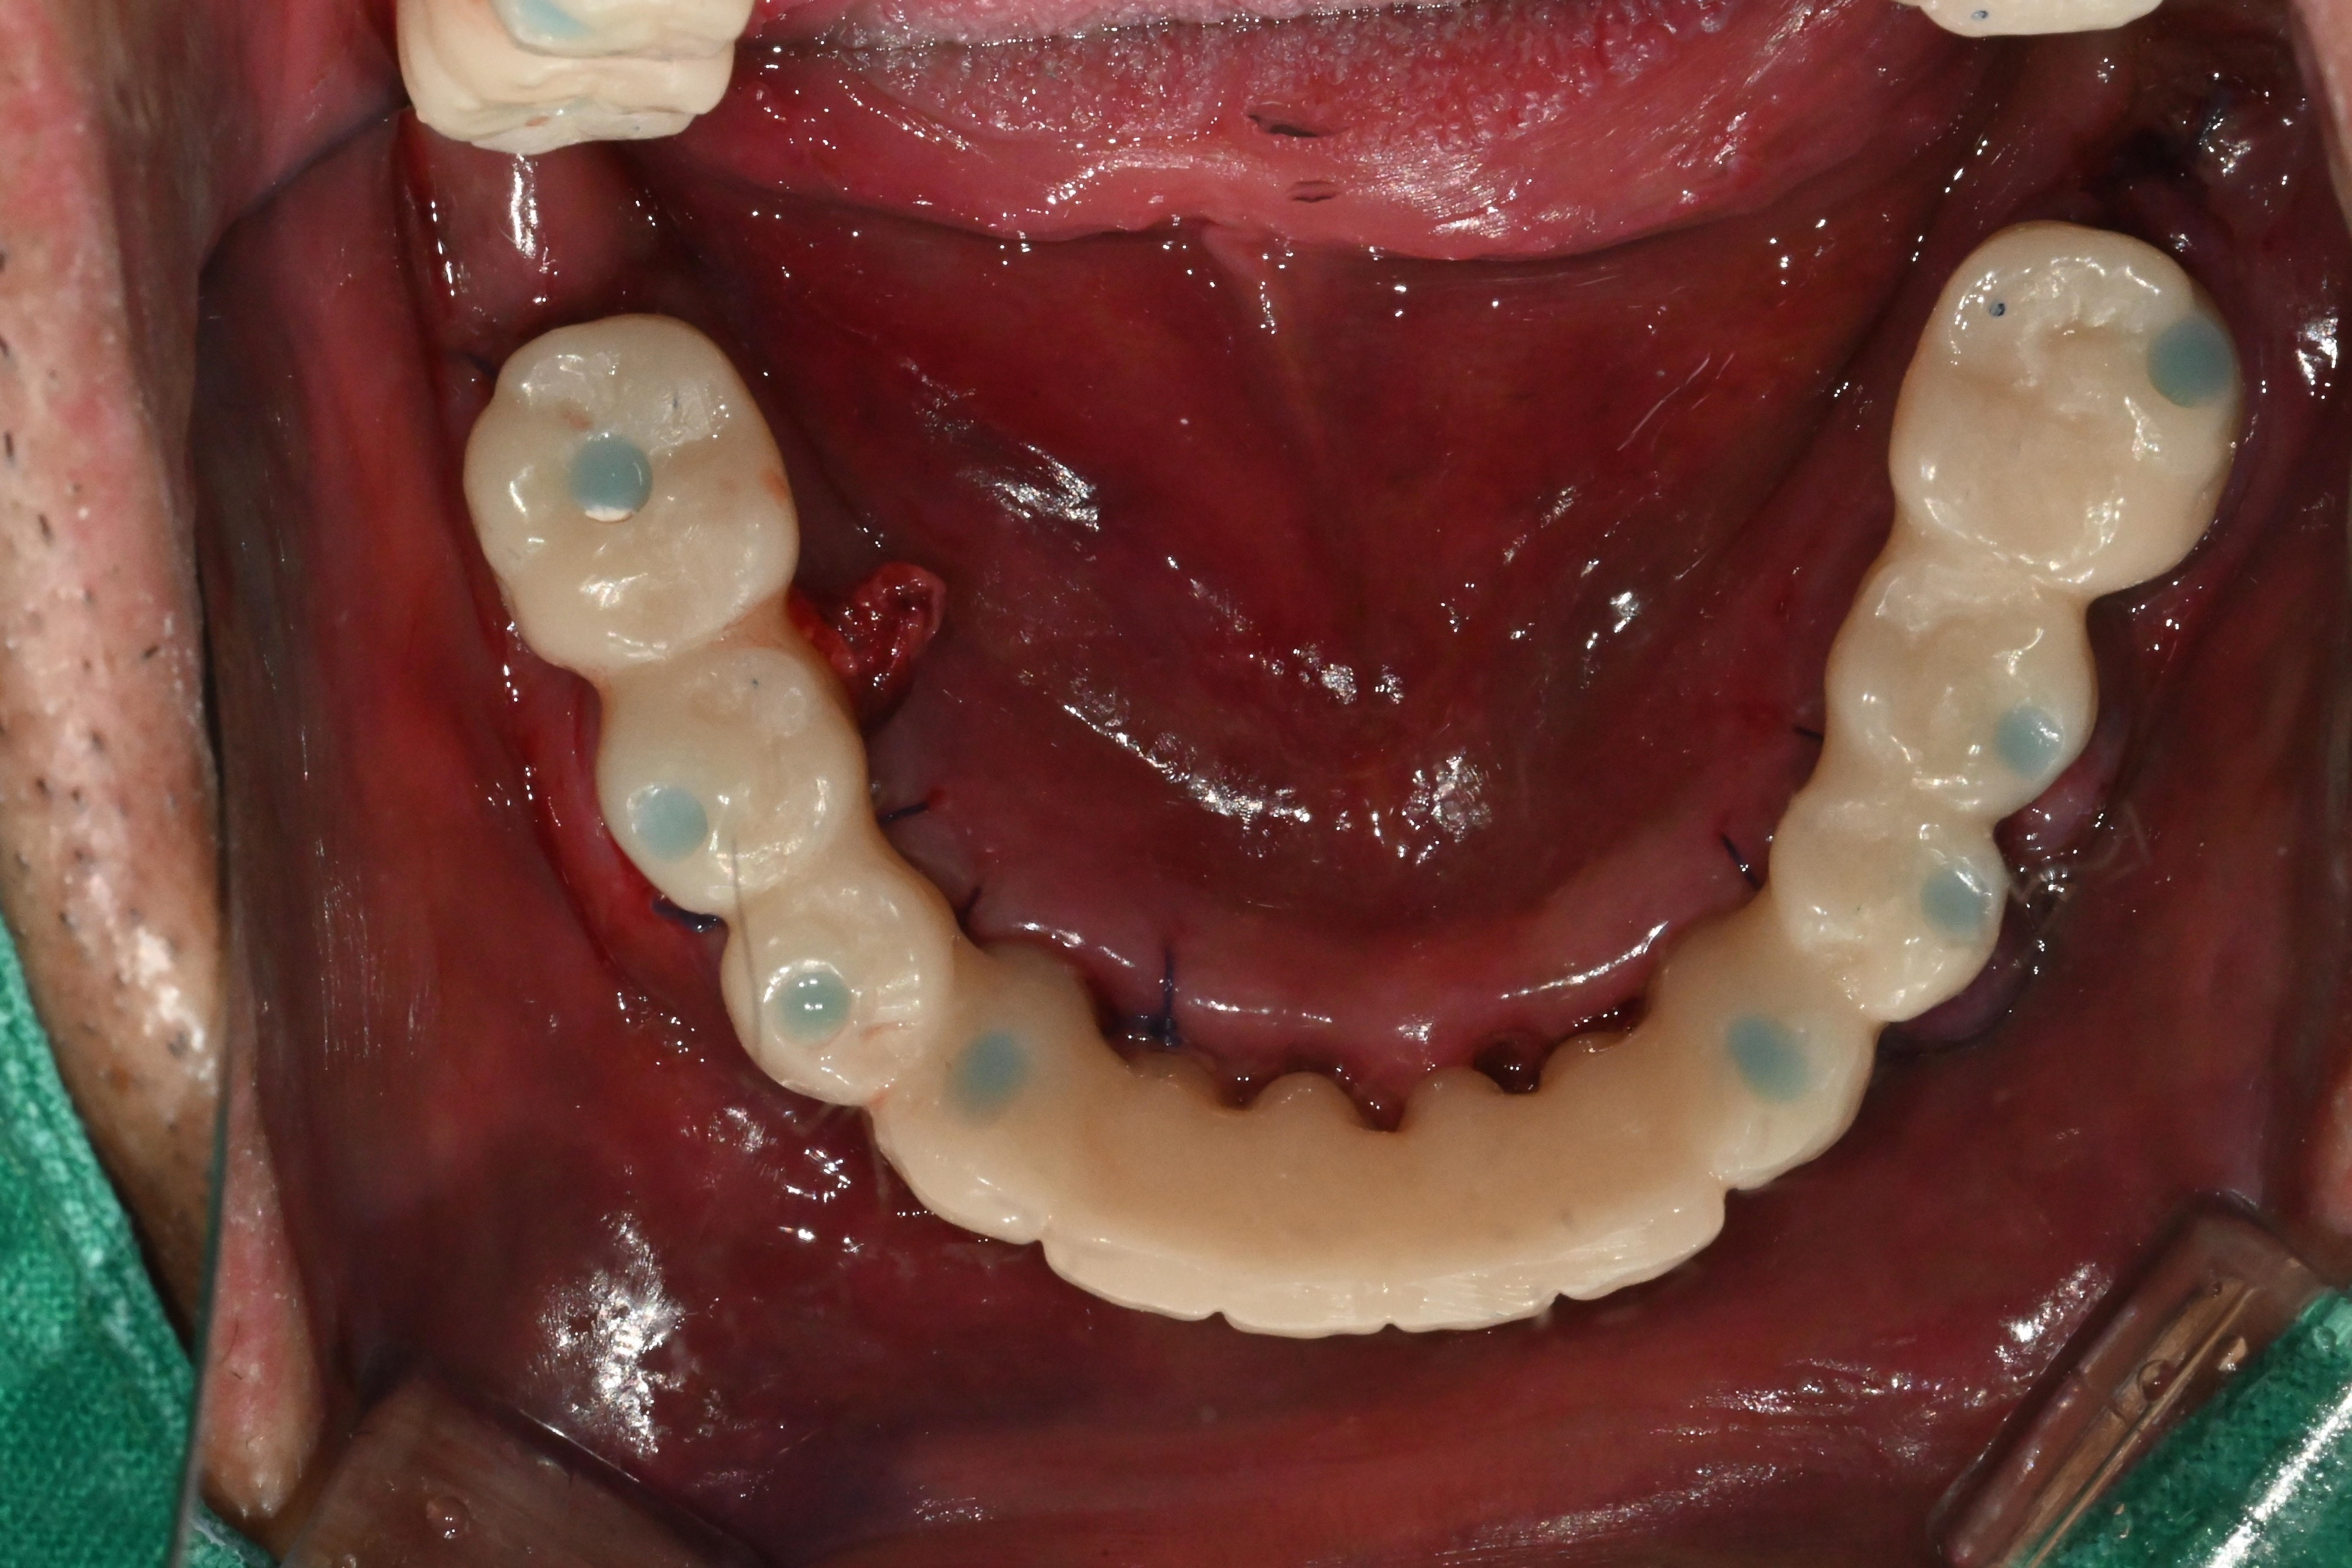

발치 12개임플란트 8개 식립

뼈 상태와 고정력이 안정적으로 나와

다음날 임시치아

바로 장착하기로 결정했습니다.

여기서 중요 포인트는,

잇몸을 누르지 않는 구조의

임시치아 라는 점입니다.

보통 치아를 바로 장착할 때는

시멘트를 사용하는 경우가 많은데,

이 시멘트가 잇몸 속에 남으면

염증을 유발할 수 있습니다.

그렇기에

시멘트 없는 구조로

장착하였습니다.

아직 실밥이

선명하게 보이는 시기지만

환자분은 바로

식사와 대화가 가능한 상태가 됩니다.